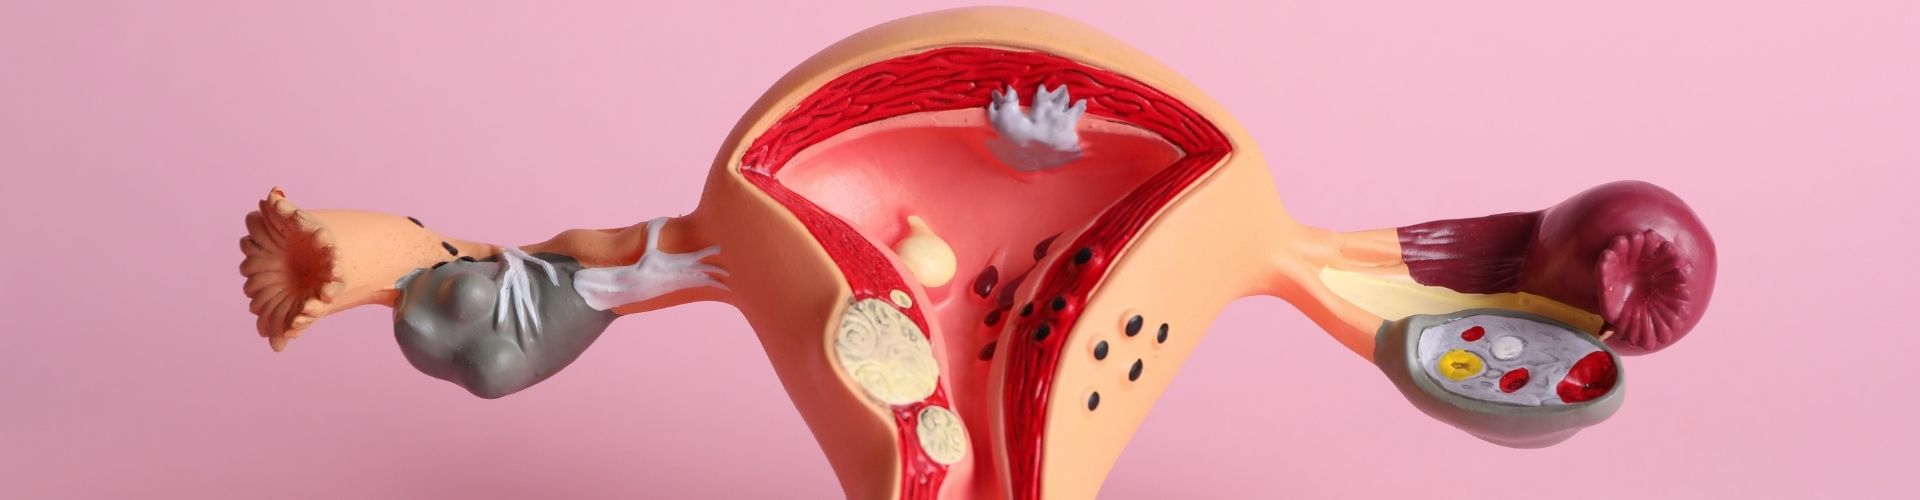

Tüplerin tıkanıklığı, kadın üreme sistemiyle ilgili önemli bir sağlık sorunudur ve doğurganlık üzerinde ciddi etkilere sahip olabilir. Fallop tüpleri veya rahim tüpleri olarak adlandırılan bu yapılar, yumurtalıklardan rahme yumurtaların taşınmasını sağlar. Ancak, çeşitli nedenlerle tüpler tıkanabilir ve bu durum, hamilelik şansını azaltabilir veya engelleyebilir.

Tüplerin tıkanıklığını tetikleyen birçok faktör vardır. Enfeksiyonlar, özellikle de pelvik inflamatuar hastalık (PID), tüplerin iltihaplanmasına ve sonrasında tıkanmasına yol açabilir. Endometriozis, rahim dışında endometrium...